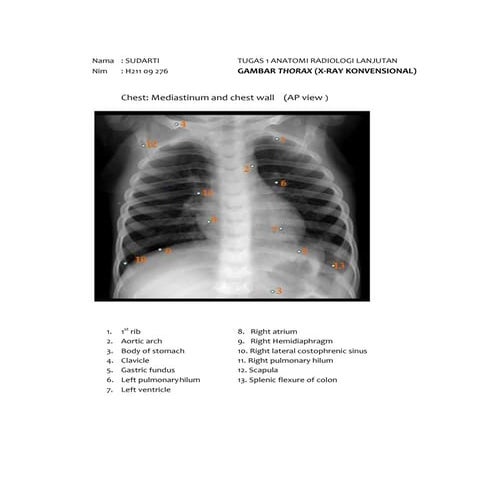

X ray (kel x)